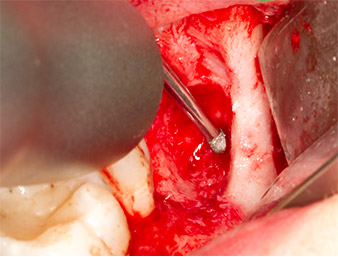

To obtain autogenous material for subsequent wound treatment, healthy bone chips were harvested from the surroundings of the root remnant with a piezo surgical instrument (Piezomed B5) (Fig. 5).

The autogenous tissue was removed with the scraper-shaped section of the working part of the instrument and stored in a physiological saline solution until further use (cf. Fig. 13).

To expose the root remnant with as little trauma as possible to the tissue, a further instrument was used (Piezomed S2) that is primarily indicated for preparing the lateral window in augmentations of the sinus floor. The diamond-coated ball was additionally used to smooth sharp bone edges (Fig. 6 and 7). All the Piezomed attachments were used with the relevant automatic default setting without booster function.